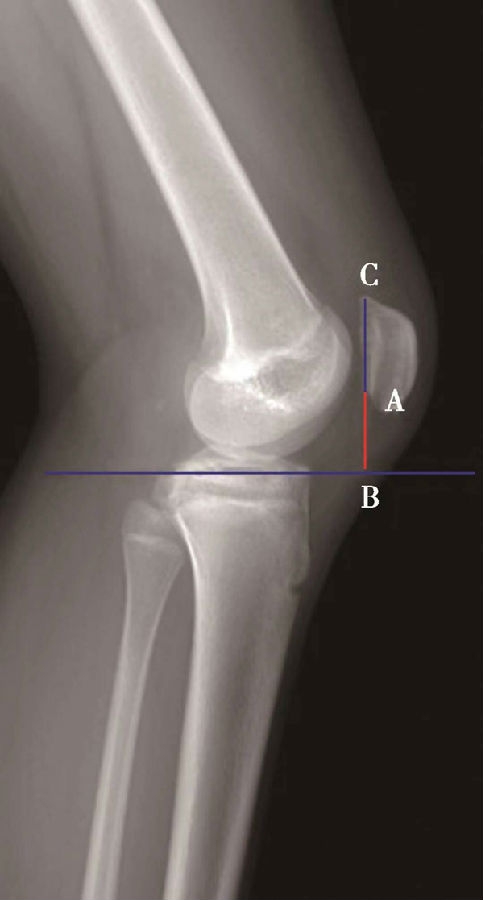

(1)Caton指数>1.2提示高位髌骨(图3),而<0.8提示低位髌骨。

如图示:AB为髌骨关节面最低点到胫骨平台轮廓前上角最短的距离,AC是髌骨关节面的长度。Caton指数=AB/AC(图1)。

图2 Caton指数=AB/AC=1.10,为正常髌骨高度

临床工作中常常使用其来估计胫骨结节移位的效果。正常人的Caton指数=1,正常范围0.8~1.2(图2)。需要注意的是:术前规划胫骨结节需要移位的理论距离为AB-AC,这就是需要将胫骨结节向远端移位的最大距离。但在术中胫骨结节转移的距离往往要小于这个距离,避免因过度移位造成医源性的低位髌骨。